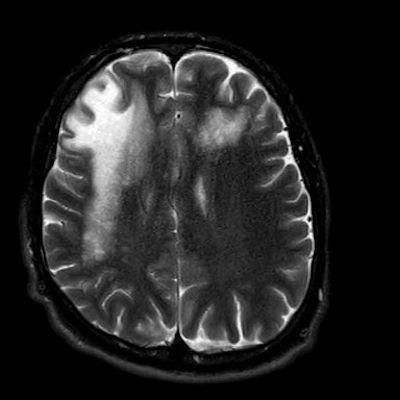

1. A) Aksiyel T2A görüntülerde bilateral sağda belirgin frontoparietal subkortikal ve derin periventriküler beyaz cevherde subkortikal U fiberleri boyunca yerleşimli sinyal artımları (oklar) izlendi.  Tarifli alanlar aksiyel T1A serilerde hipointens görünümde (oklar) izlendi.

1. PML’de MRG bulguları genellikle multifokal, asimetrik periventriküler ve subkortikal beyaz cevher tutulumu şeklindedir. Subkortikal U-fiberleri sıklıkla tutulur, özellikle parietooksipital bölgelerde belirgin lezyon eğilimi vardır.

2. T1 ağırlıklı görüntülerde tutulan bölgeler hipointens, T2A’da ise hiperintens izlenir. Ana lezyon çevresinde çok sayıda noktasal (milkyway) sinyal artımları görülebilir. Ayrıca spleniumu çaprazlayan parietooksipital sinyal değişiklikleri (barbell bulgusu) ve dentat nukleusu koruyarak serebellar beyaz cevher tutulumu (shrimp bulgusu) da tanımlanmıştır.

3. Kontrastlı incelemelerde genellikle kontrast tutulumu izlenmez. Diffüzyon görüntülemede özellikle lezyonun ilerleyen periferik alanlarında yamalar halinde diffüzyon kısıtlılığı izlenir. MR spektroskopide NAA azalması, laktat varlığı ve artmış kolin ve lipid düzeyleri görülür. MR perfüzyonda ise lezyonların ilerleyen kenarında perfüzyon artışı saptanabilir.

4. Bizim hastamızda bilinen HIV enfeksiyonu mevcuttu ve yapılan kraniyal MR görüntülemede multifokal, asimetrik, periventriküler ve subkortikal beyaz cevherde yerleşimli, kitle etkisi göstermeyen ve kontrastlanmayan lezyonlar izlendi. Lezyonların subkortikal U-fiberleri tutması ve özellikle parieto-oksipital bölgelerde belirgin olması nedeniyle ön planda PML düşünüldü. Histopatolojik tetkik ile PML tanısı doğrulandı.